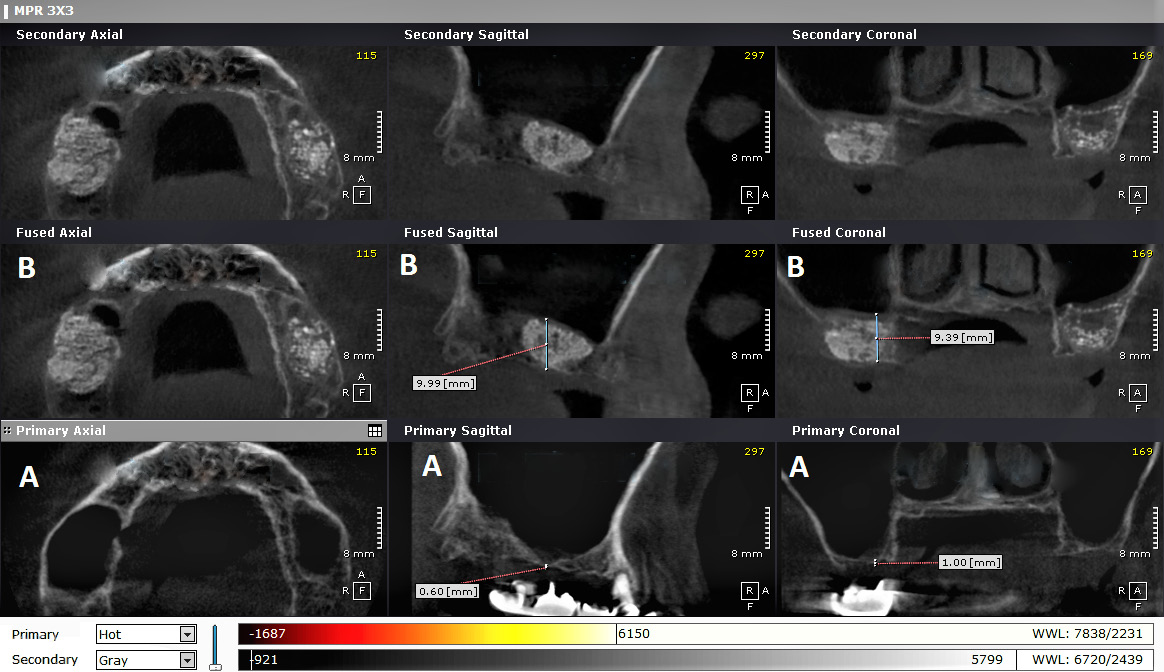

Three CBCT radiographs were performed for each patient with the use of the PaX-i3D Green imaging system (Vatech, Hwaseong, South Korea). All scans were conducted in the same radiology center to standardize the characteristics of the radiographs, with the same position being repeated pre-op (T0), immediately post-op (T1) and 6 months post-op (T2), i.e., before the 2nd surgical operation (implantation).

The radiographs were examined using the OnDemand3D program (https://www.ondemand3d.com/en), which enabled standardization by merging the 2 radiographs (taken at T0 and T1) to ensure the measurements of the same site on both scans, and to avoid any changes that could be caused by altering the position of the patient’s head (Figure 9).

The 1st image (T0) allowed the measurement of bone height before the maxillary sinus lift, using points in the sagittal view. The 3rd image (T2) was used to measure the amount of lifting at the same sites.

Bone height was measured on the 1st image (T0) at 5 locations in the coronal view, where each point in the coronal view matched the corresponding point in the sagittal view, using the ‘ruler’ tool. Bone height was also measured on the 3rd image (T2) at 5 locations in the coronal view. Using the same method, we measured bone height in the sagittal and coronal views on the 2nd image (T1).